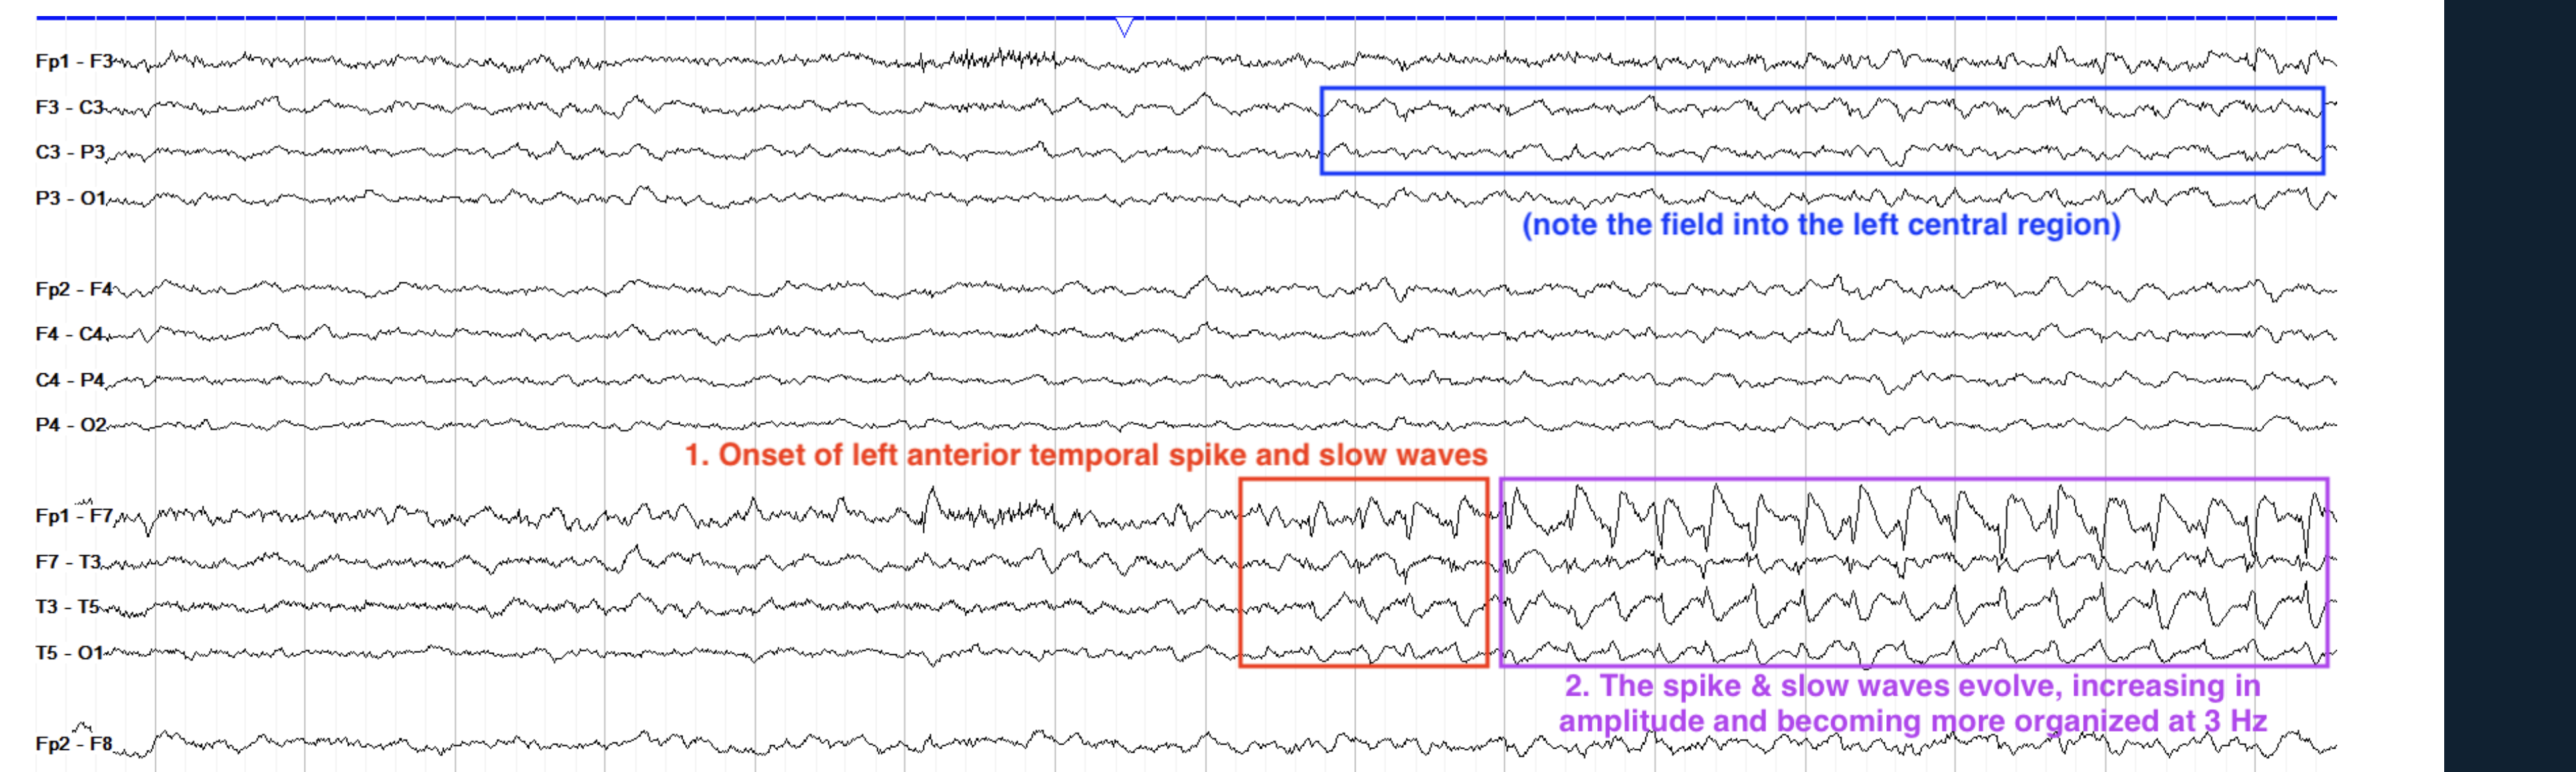

alpha. theta/field left centrtal

focal seizuere